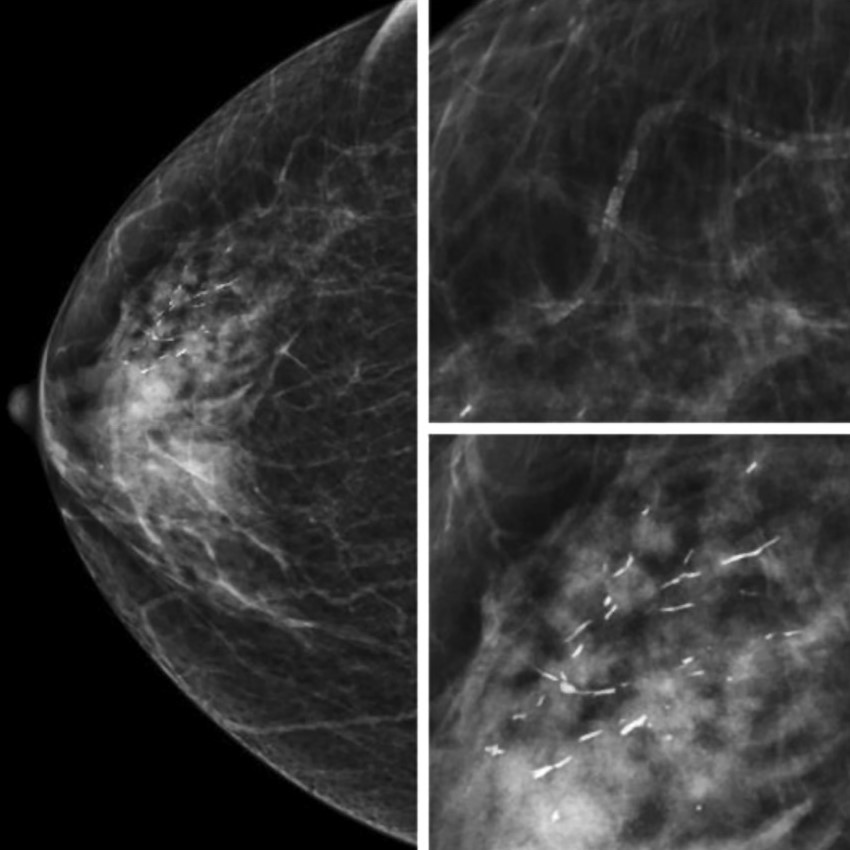

Сосудистые кальцинаты определяются на маммограммах как параллельные гиперденсные линии по ходу стенок сосудов. Их также называют кальцинатами Мёнкеберга, они поражают среднюю оболочку сосуда [13, 14] (Рис.2).

Внутрикожные кальцинаты локализованы преимущественно в дерме и являются результатом обызвествления протоков сальных желез. Чаще всего локализуются группами, имеют кольцевидную или точечную форму (Рис.3).

Для фиброзно-кистозных изменений характерны кальцинаты по типу Weddell. Как правило, они имеют квадратную, треугольную или трапецивидную форму (Рис.4).

Округлые кальцинаты с просветлением в центре, кальцинаты по типу «яичной скорлупы» характерны для обызвествления макро- и микрокист (Рис.5).

Кроме того, для обызвествления мелких кист молочной железы характерны кальцинаты по типу «молочка кальция». Образуются в результате седиментации кальция в структуре кисты и имеют форму чашечки или полумесяца в боковой проекции (Рис.6).

Множественные рассеянные точечные микрокальцинаты характерны для склерозирующего аденоза – доброкачественного состояния, при котором отмечается увеличение долек молочных желез и их дисторция окружающей фиброзной тканью [13] (Рис.7).

Глыбчатые микрокальцинаты с множественными просветами внутри характерны для обызвествленных папиллом (Рис.8).

При инфильтрации перидуктальной стромы плазматическими клетками и пролиферации клеток базальной мембраны протоков образуются линейные, стержневидные кальцинаты ориентированные по ходу протоков. Такая картина патогномонична для перенесенного плазмоклеточного мастита (Рис.9).